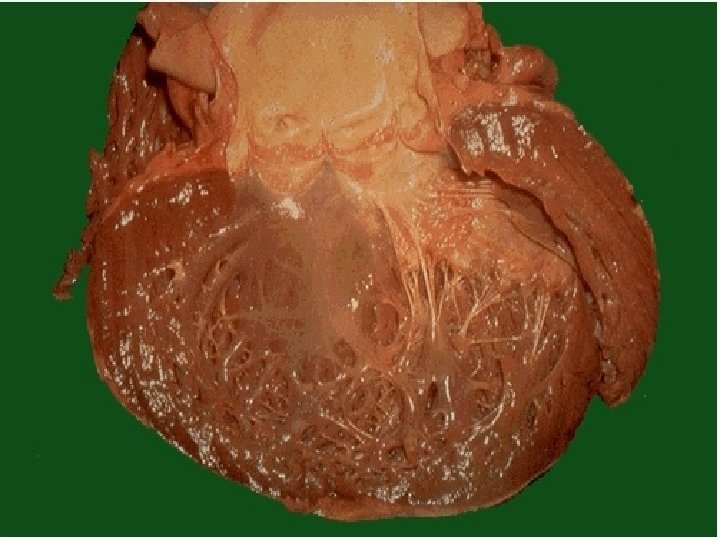

DISFUNCION SISTOLICA: • Disminución de la función de bomba, con disminución de la fracción de expulsión (< 50%). • Etiología: Cardiomiopatía dilatada, Cardiopatía Isquémica, Hipertensión, Valvulopatías.

DISFUNCION DIASTOLICA: • Trastorno en la relajación con llenado anormal que produce congestión pulmonar y disminución del volumen sistólico. • Etiología: Hipertensión, Cardiopatía Isquémica, Cardiomiopatía Hipertrófica, Cardiomiopatía Restrictiva

Fisiopatología: Los principios básicos en la IC son la retención de sodio y agua con la consecuente congestión pulmonar y el edema periférico. Este aumento de retención líquida corporal es el resultado de la disfunción ventricular (bajo gasto cardiaco).